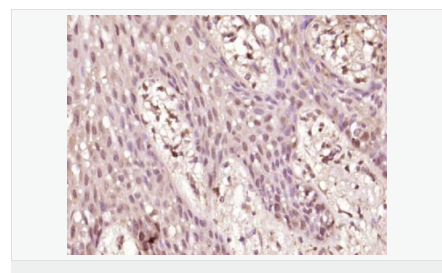

| 產(chǎn)品應(yīng)用 | WB=1:500-2000 ELISA=1:5000-10000 IHC-P=1:100-500 IHC-F=1:100-500 Flow-Cyt=1μg /test IF=1:100-500 (石蠟切片需做抗原修復) not yet tested in other applications. optimal dilutions/concentrations should be determined by the end user. |